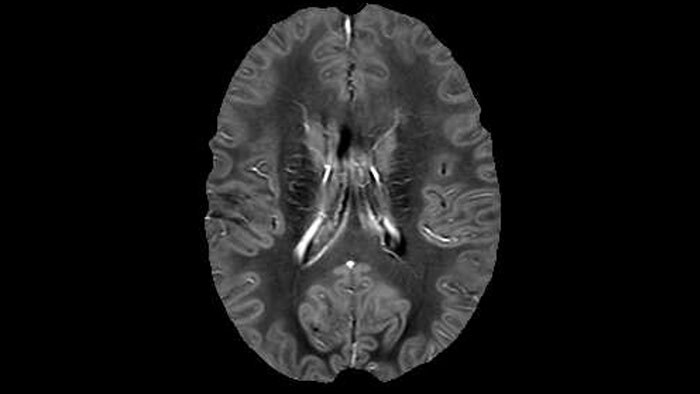

Magnetic resonance imaging

Discover Philips MRI systems and solutions that deliver high-quality diagnostic imaging, improve productivity and enhance the overall experience.